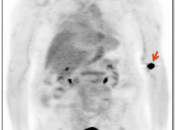

Extravasation of Injected FDG

FDG is injected intravenously. As many cancer patients have challenging venous access issues, partial extravasation of FDG during injection is not uncommon (an estimated 10% of patients have evidence of extravasation on their PET images).

Extravasation of FDG at the time of the intravenous injection can result in false positive interpretations due to:

- Focal intense uptake at the injection site.

- Linear uptake along the lymphatic channels within the arm (appearing as long vessels).

- Focal uptake in small ipsilateral axillary nodes.

If these nodes are enlarged, be cautious before dismissing them as “injection-related”. We have seen more than one case of a radiologist calling axillary nodes “injection-related”, when the patient was injected in the opposite arm.